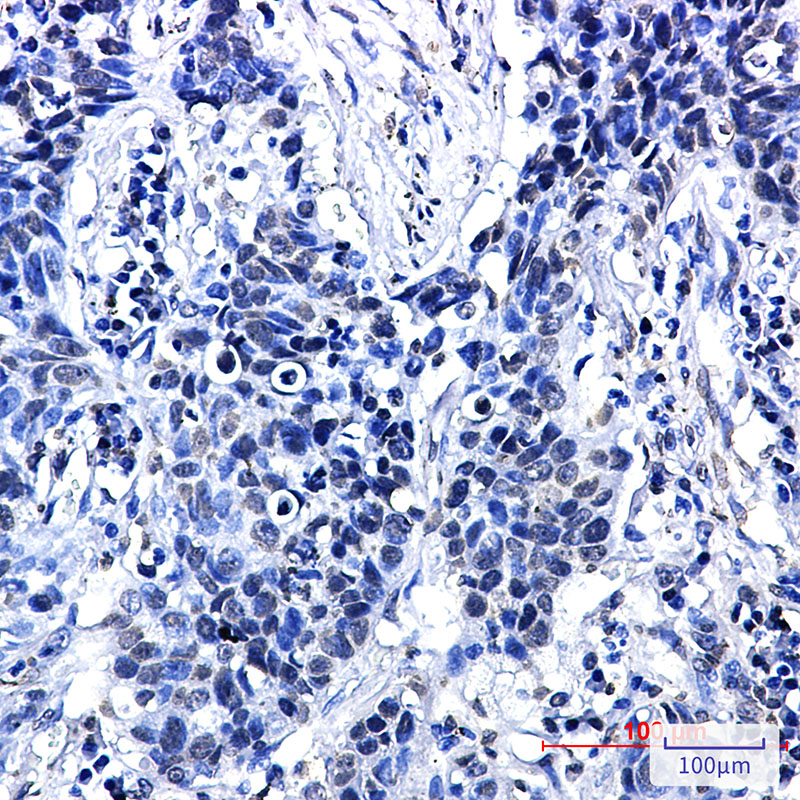

- Immunohistochemistry analysis of paraffin-embedded Human lung cancer using Phospho-delta 1 Catenin/CAS (Thr916) antibody.High-pressure and temperature Sodium Citrate pH 6.0 was used for antigen retrieval.